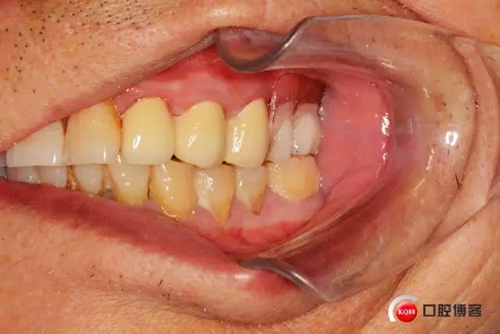

主訴:求鑲牙,解決咀嚼功能及食物嵌塞問(wèn)題

兩年前患者外院口腔鑲固定義齒修復(fù)使用不久牙冠脫落基牙折斷,又繼續(xù)修復(fù)可摘局部義齒,惡心、無(wú)法咀嚼且食物嵌塞嚴(yán)重,前來(lái)本院求重新修復(fù)。

患者初診口腔情況15號(hào)牙為原做可摘局部義齒做卡環(huán)預(yù)備,真“專家”的活